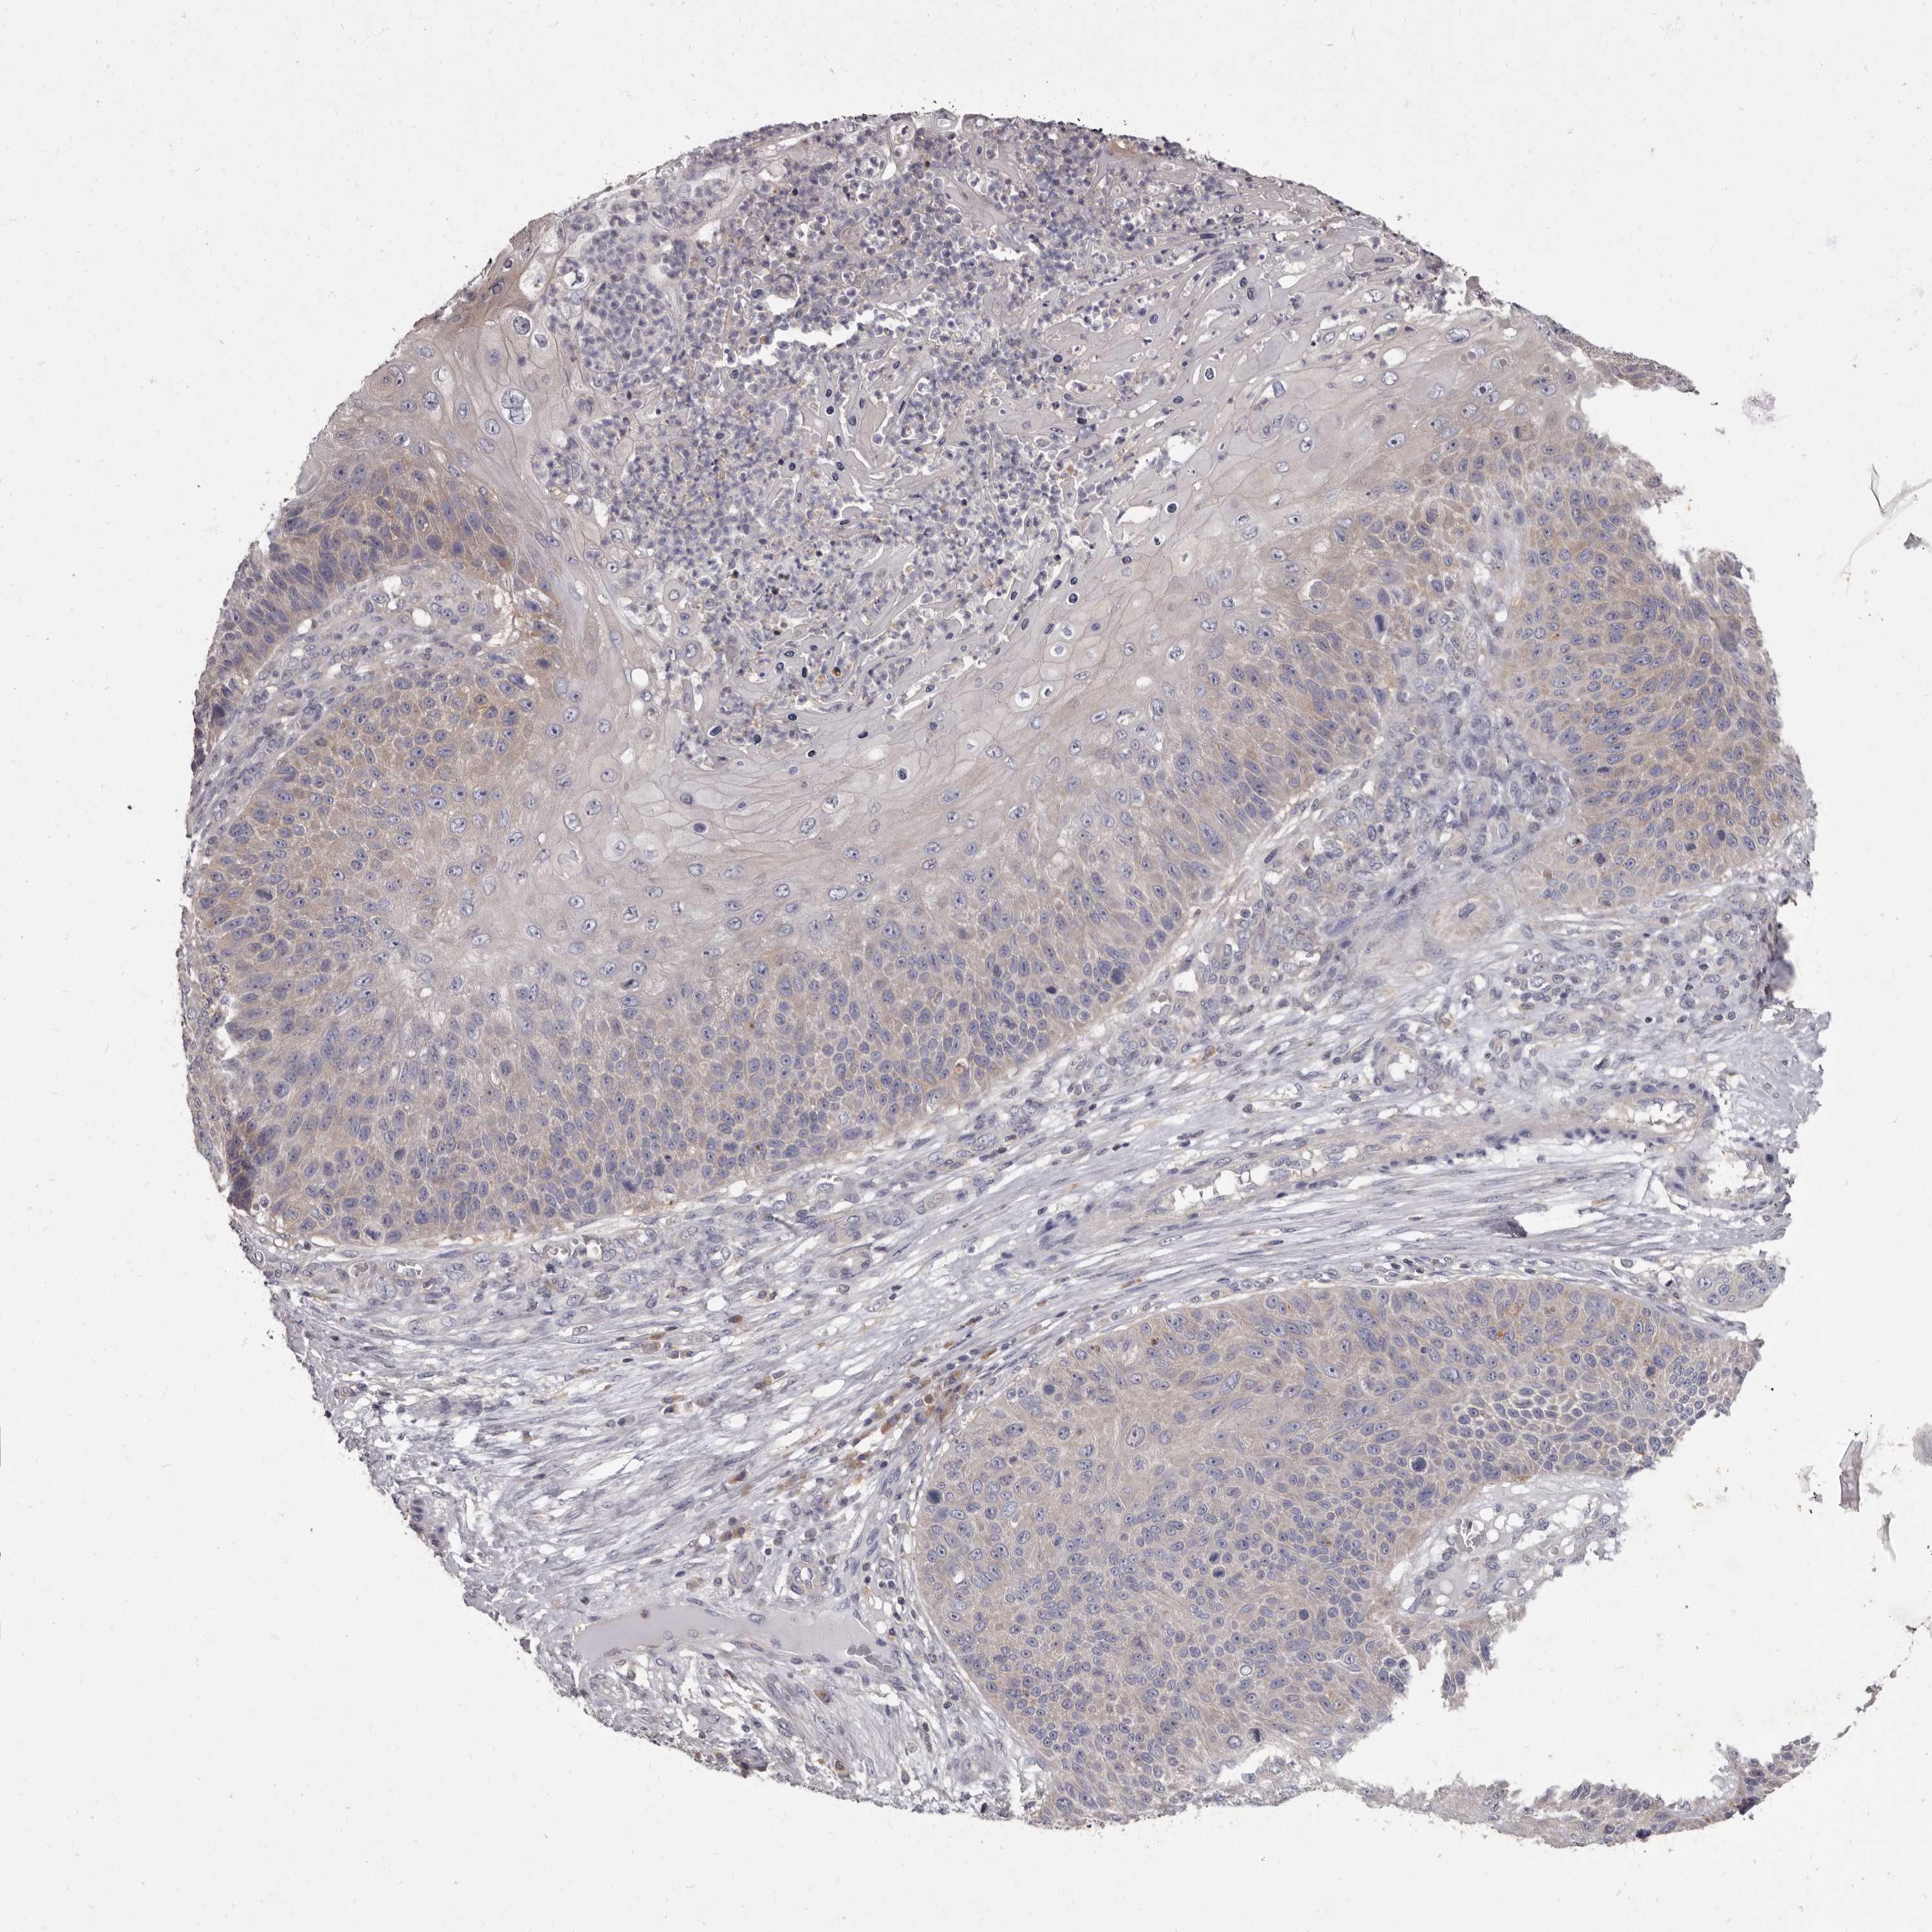

SKIN CANCER - Protein expressioni

A mouse-over function shows sample information and annotation data. Click on an image to view it in a full screen mode. Samples can be filtered based on level of antibody staining by selecting one or several of the following categories: high, medium, low and not detected. The assay and annotation is described here.

Each image is clickable and will lead to virtual microscopy that enables deeper exploration of all samples and also displays staining intensity scores, fraction scores and subcellular localization as well as patient and tissue information for each sample.

Antibody HPA029700

Antibody HPA029701

Antibody HPA029702

Antibody HPA029703

Staining

High

Medium

Low

Not detected

Intensity

Strong

Moderate

Weak

Negative

Quantity

>75%

75%-25%

<25%

None

Location

Nuclear

Cytoplasmic/membranous

Cytoplasmic/membranous,nuclear

Basal cell carcinoma

Squamous cell carcinoma, NOS

Squamous cell carcinoma, metastatic, NOS